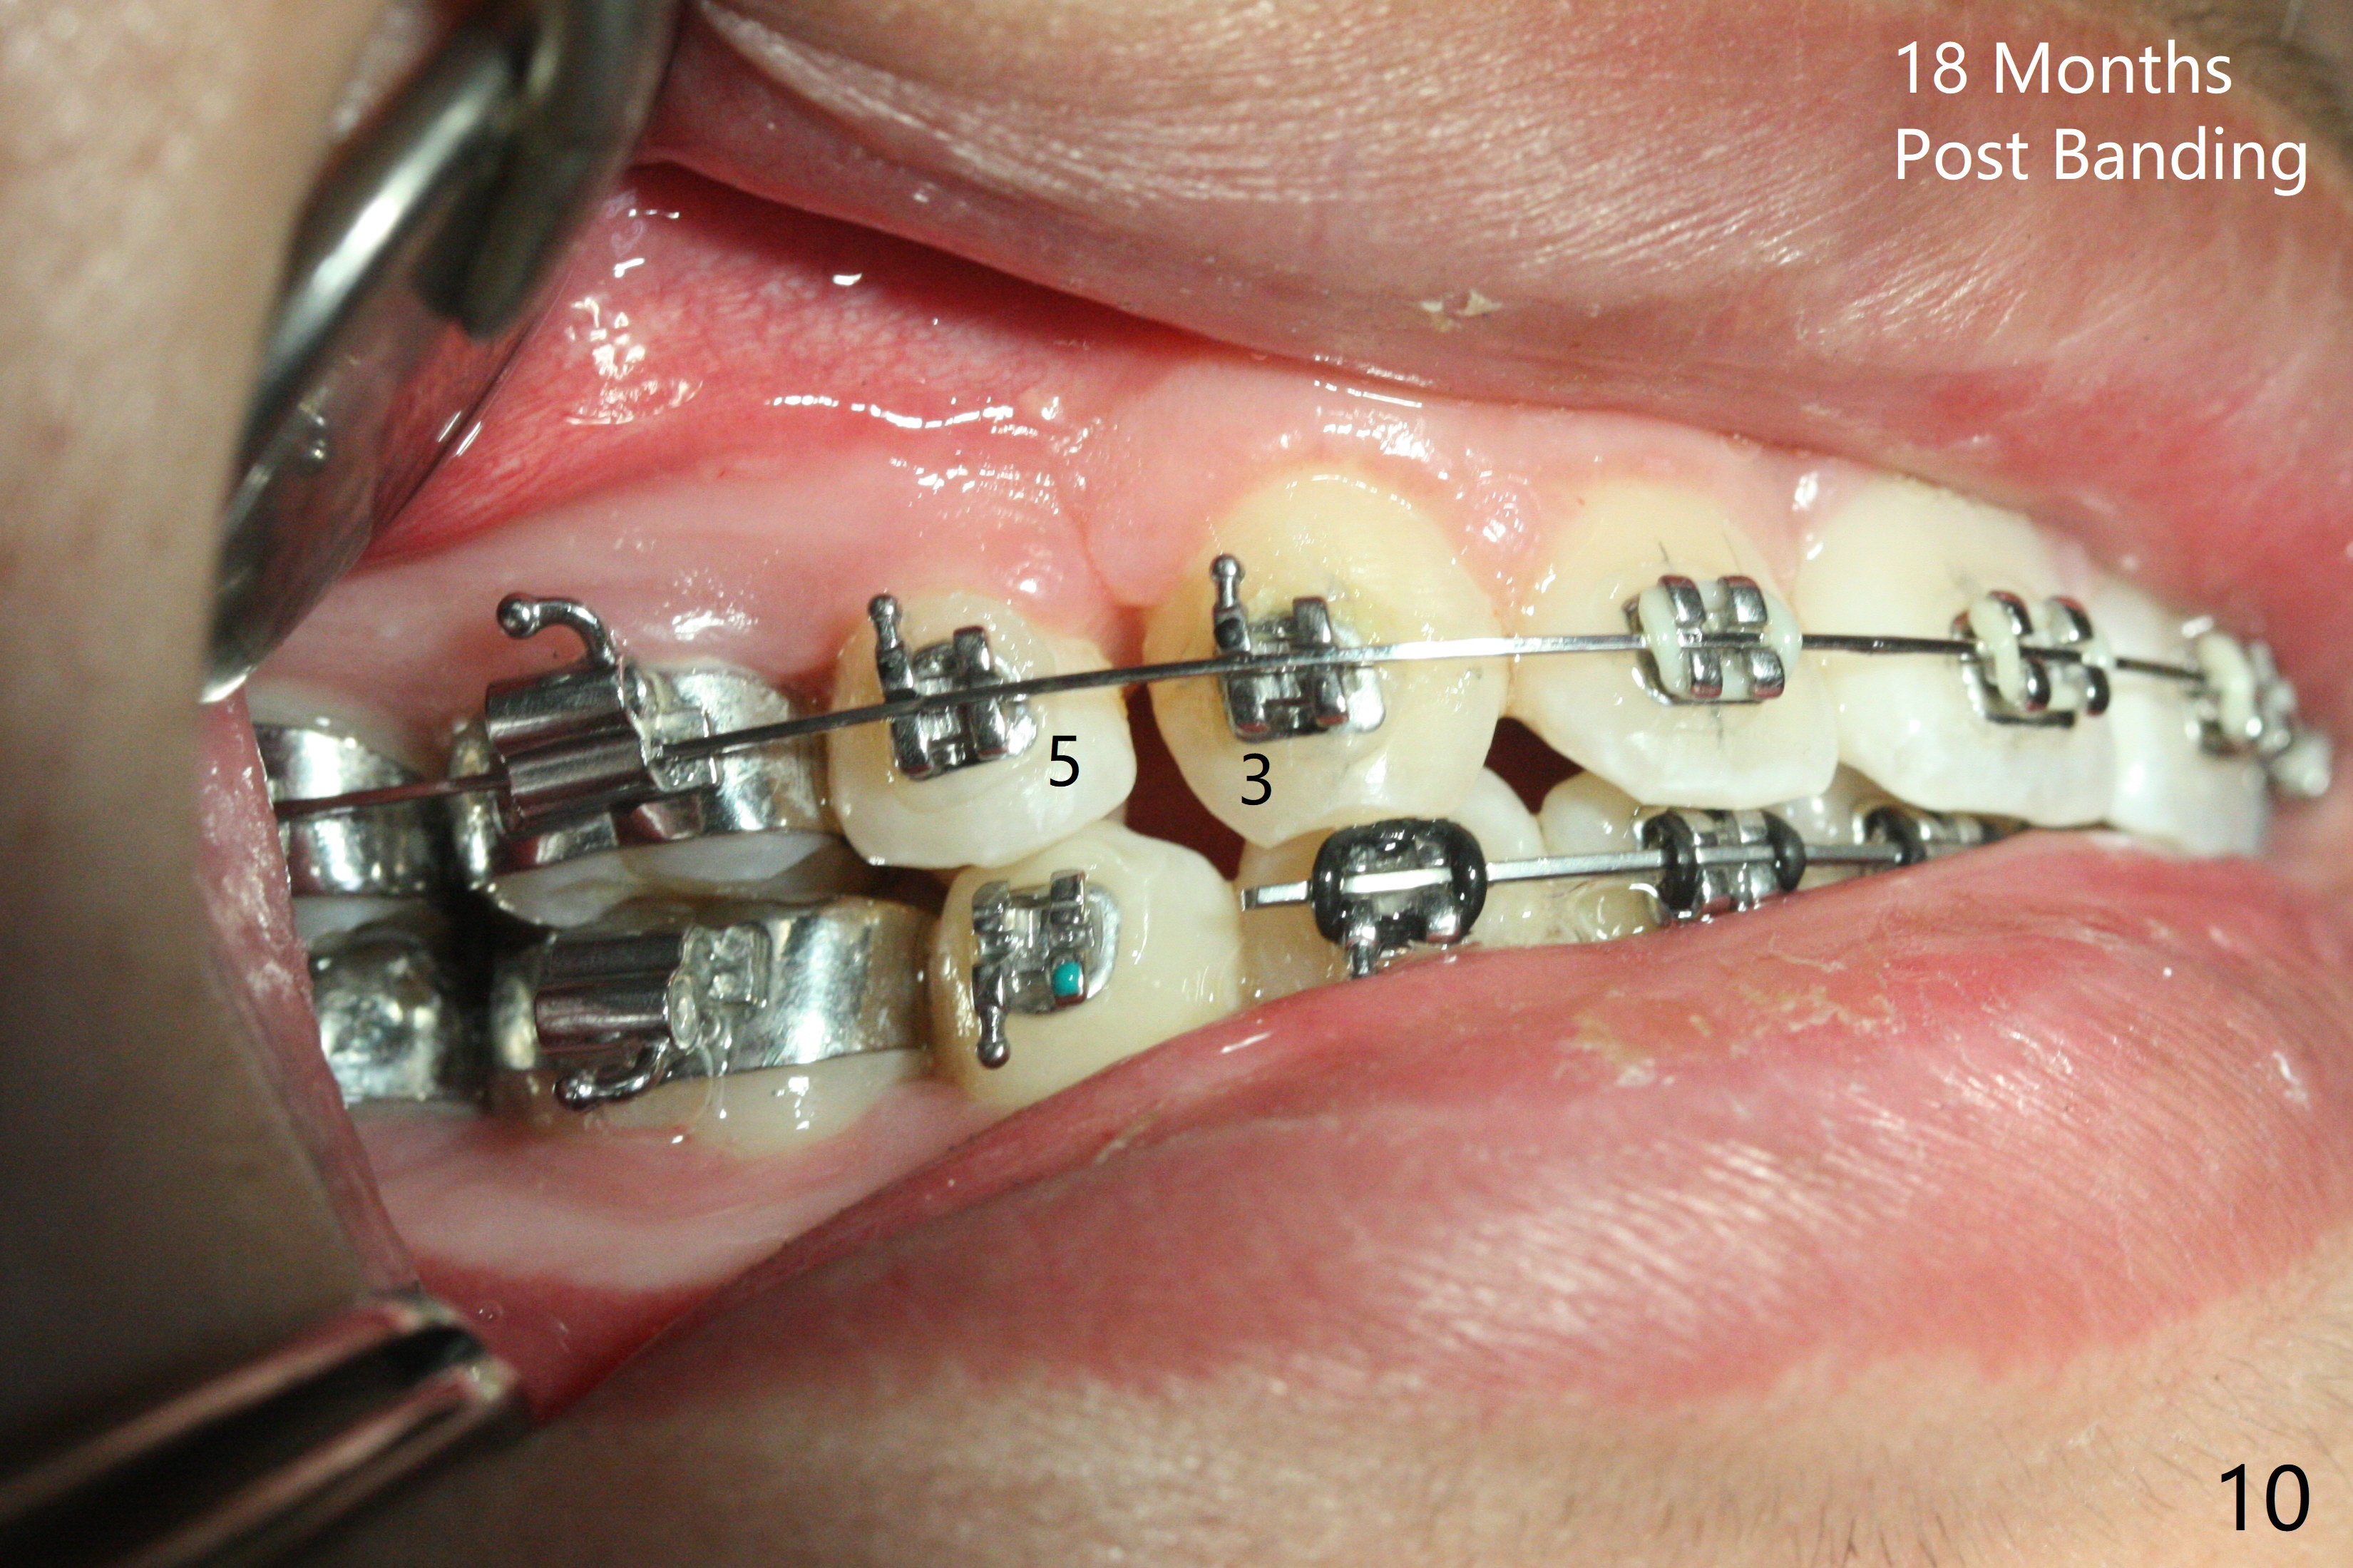

After use of segmental wires (Fig.10 ) with posterior interdigitation, diastemata between U3/5 re-appear with the upper dental midline deviation to the left.